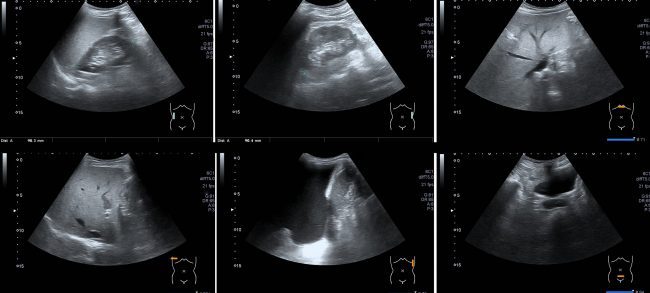

Sonographie

Die Sonographie oder Ultraschalluntersuchung (beides bezeichnet das Gleiche) ist ein Verfahren, welches OHNE die Anwendung von Röntgenstrahlen erfolgt. Die Untersuchung wird in einem meist gut abgedunkelten Raum durchgeführt. Die Patientin / der Patient werden auf einer bequemen Liege entsprechend der zu untersuchenden Körperregion gelagert. Die Radiologin / der Radiologe bedient ein PC-ähnliches Gerät, in welchem…